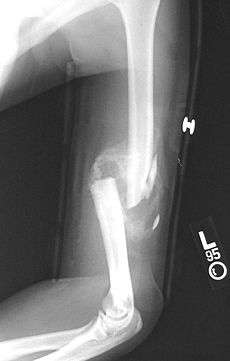

A transverse fracture of the humerus shaft

A spiral fracture of the humerus shaft